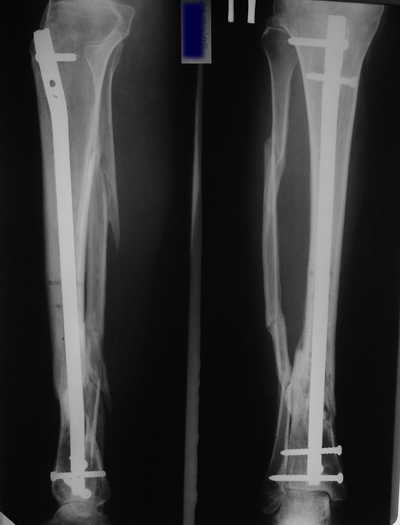

Мужчина, 33 года, резекция б\б кости по поводу остеомиелита после открытого перелома. Стандартная методика билокального остеосинтеза (рис 1 и 2). В конце удлинения выявилось неудовлетворительное взиморасположение перемещенного фрагмента и дистального отломка (рис 3). Планирование (рис 4).

Адаптация отломков гексаподом за 5 дней (рис 5). Замена гексапода на обычные штанги (рис 6 и 7)